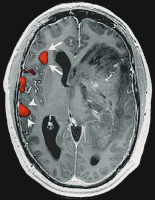

Brain tumour

Figure 2: Brain tumour localised in the left temporal lobe of a left-handed patient. fMRI activation of a verb-to-noun generation is present in the expressive language area in the inferior frontal gyrus (arrow), as well as in the receptive language areas in the posterior temporo-parietal cortex (arrowheads). Activation is more pronounced in the left hemisphere, indicating a left-lateralised hemispheric language representation.

Keywords: brainfMRITumor